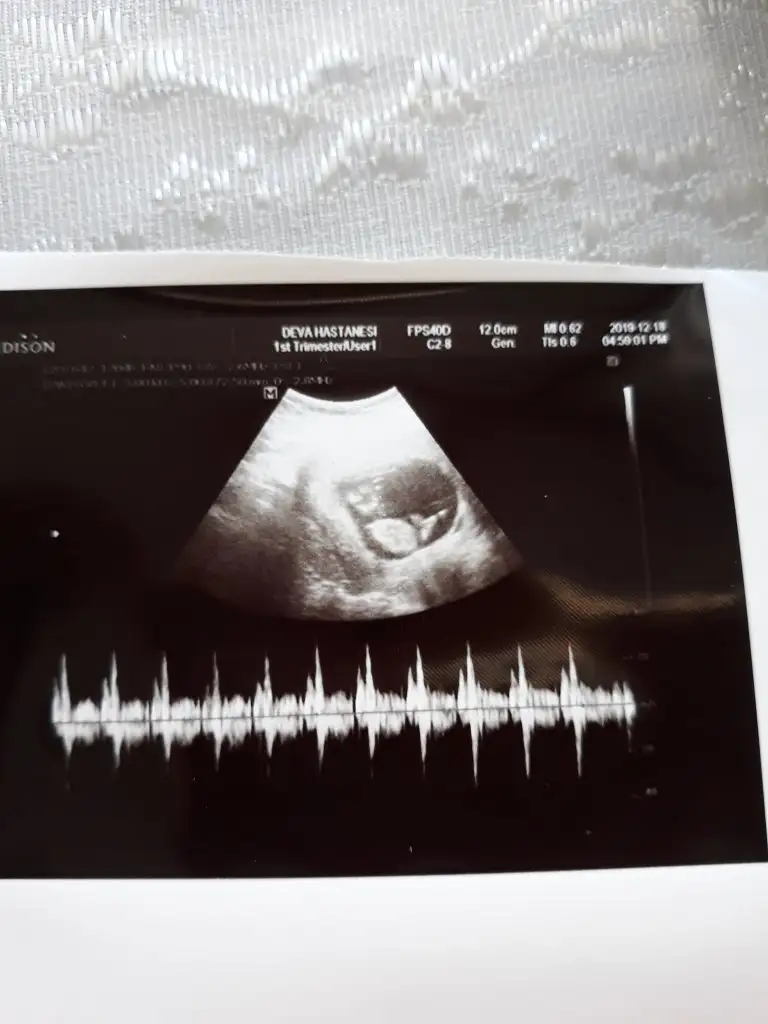

Bunada bakarmisiniz 12 +2 haftalık cok merak ediyorum🙏😊

• 20191218_102250.webp

20191218_102250.webp

16,6 KB · Görüntüleme: 71

Doktor %80 erkek dedi sizce net midir? Cok arkdsm

Bu haftalara guvenme her gittigimde farkli sey soyluyor doktor dedi nuba gorede erkek gibi ama merak ediyorm onceden boyle olup sonra kiz cikan var mi?